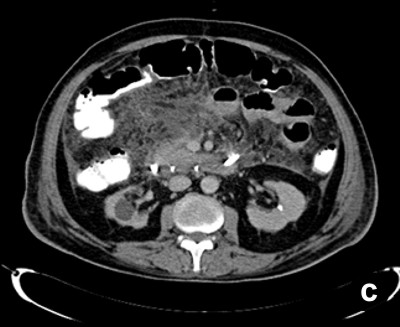

Twenty-four patients (48.0%) underwent image-guided drainage of the pancreatic/peripancreatic collections. Nine of these patients (37.5%) were successfully managed by radiological intervention only (Figure 2) while 15 (62.50%) continued to have or developed infection, persistent organ failure or locoregional complications. These 15 patients were subsequently operated upon (Figure 3). There were a total of 11 procedure-related complications in these patients (73.3%) with two patients having catheter slippage which required repositioning (Table 1).

Figure 3. a. Well-defined collection within the pancreas in a patient with gallstone-induced pancreatitis on the 21st day (nasojejunal tube is seen in the duodenum). b. Percutaneous catheter inserted the next day. c. Sixteen days later, the collection showed regression but the inflammation persisted. The patient had deteriorated and was operated on. |